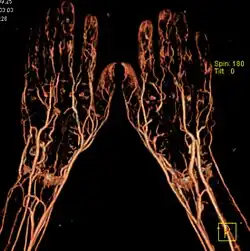

Die Bildgebung mit Röntgen-Kontrastmittel (KM) basiert darauf, dass diese die Röntgenstrahlen stärker absorbieren als die Umgebung. Im Wesentlichen wird dies durch den hohen Jodgehalt erreicht.[7] Daneben werden bariumsulfathaltige Suspensionen oder Xenon eingesetzt. Sie verbessern die Darstellung von Strukturen und Funktionen des Körpers bei bildgebenden Verfahren wie Röntgendiagnostik, Magnetresonanztomographie (MRT) und Sonografie (Ultraschall). Prinzipiell kann jede Arterie zu diesem Zwecke punktiert und einer Injektion unterzogen werden.